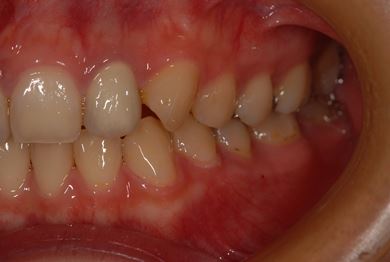

| 性別/年齢 | 女性 / 21歳 | ||||||||||||||||||||||||||||||||

| 主訴 | 現在、金属の入っている歯が虫歯になっているようなので、治してセラミックにしたい。 | ||||||||||||||||||||||||||||||||

| 治療方針 | セラミック治療にて審美的回復を行う。 | ||||||||||||||||||||||||||||||||

| 治療内容 | ハイブリッドセラミックインレー6本 | ||||||||||||||||||||||||||||||||

| 総治療費 | 189,000円 | ||||||||||||||||||||||||||||||||

| 治療期間 | 3ヶ月 |